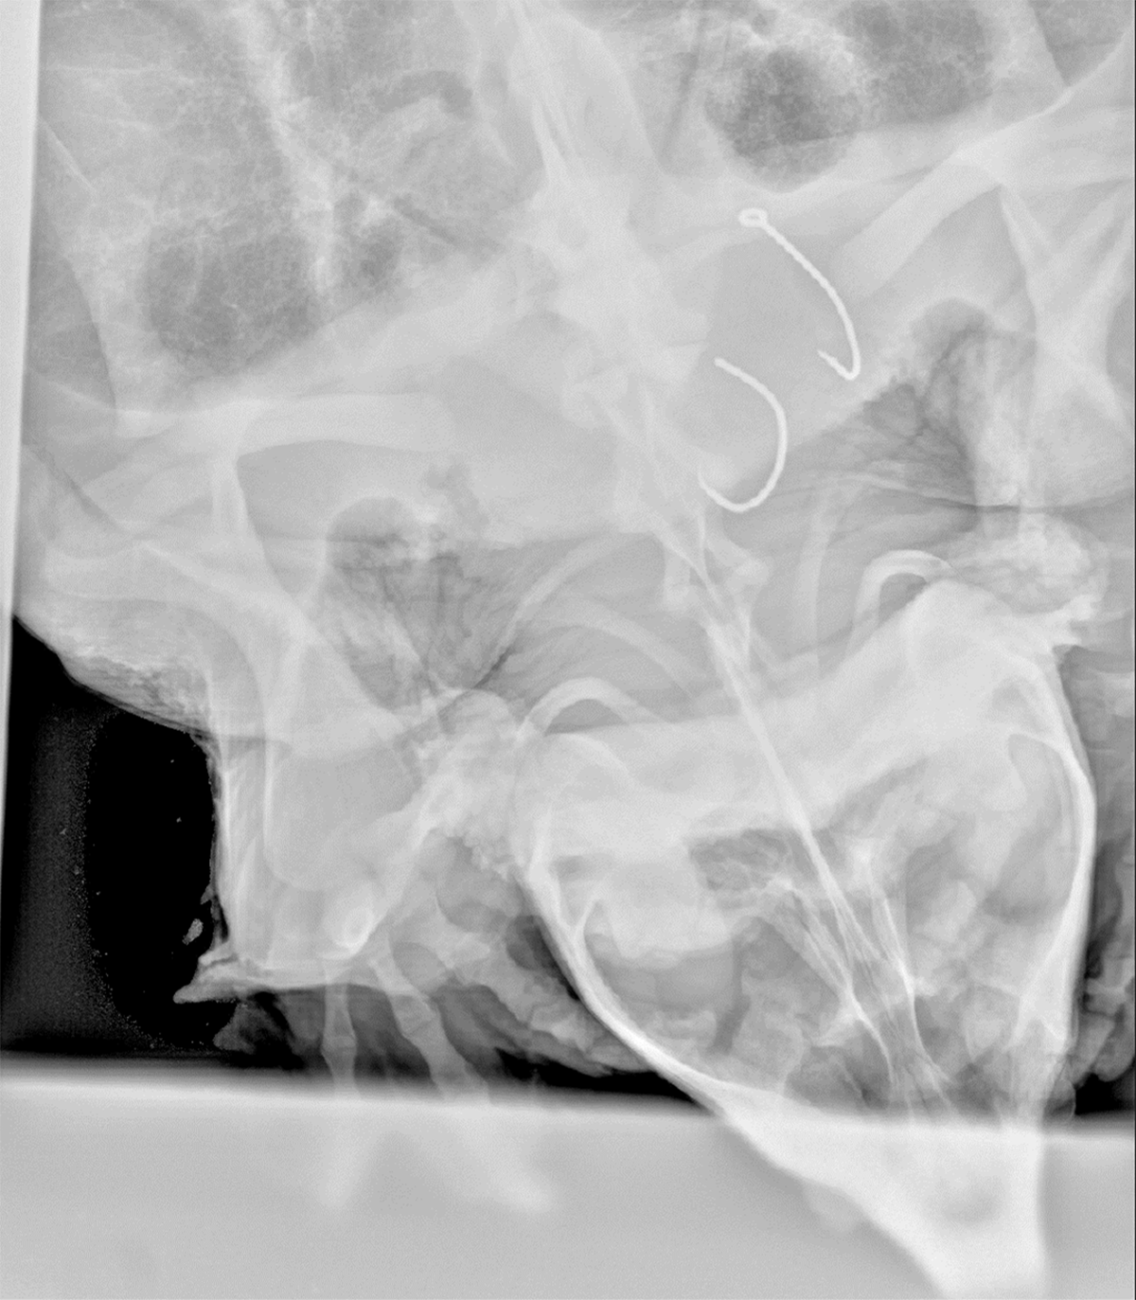

An x-ray image shows a 75-pound male alligator snapping turtle from the Big Black River, Miss. with two hooks in his throat August 7, 2024. (Photo by Luke Pearson, USFWS)